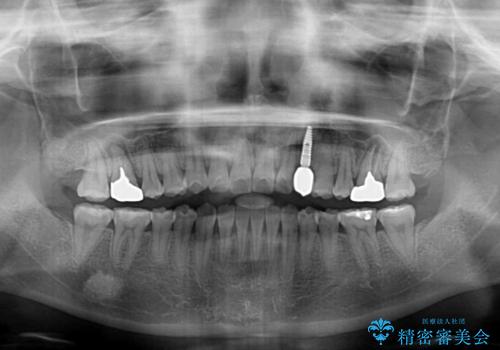

矯正治療と並行してインプラントによる補綴治療を行うこととしました。

矯正治療が終わるタイミングに合わせてインプラントの埋入を行っていたので、矯正治療を終了すると同時にセラミック補綴治療を行えました。